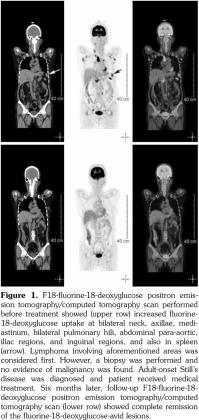

A 53-year-old female patient suffered from pain over most of her body, particularly the joints and the throat. In addition, skin rashes on the trunk without pruritus were noted. She had visited the Rheumatology, Neurology, and Orthopedic Outpatient Department several times. A chest computed tomography (CT) was performed which revealed multiple lymphadenopathies over cervical, mediastinal, and axillary areas. A positron emission tomography (PET)/CT revealed increased fluorine-18-deoxyglucose (FDG) uptake in many lymph nodes including the bilateral neck, axillae, mediastinum, bilateral pulmonary hili, abdominal paraaortic region, iliac regions, and inguinal regions as well as the bone marrow and the spleen (Figure 1). In addition, mild and diffuse increase of FDG uptake in the bone marrow was noted. Lymphoma was suspected first. After discussing with the patient, thoracoscopic mediastinal lymph node biopsy was performed. Fifteen lymph nodes were taken and the results showed histiocytic infiltration in sinusoid area and anthracotic pigment deposition. Reactive lymphoid follicle hyperplasia and focal fibrocalcified nodule formation were also noted. No tumor cell was seen. Gallium-67 (Ga-67) scan was conducted and no gallium-avid tumor was seen throughout the whole body (Figure 2). The laboratory data were negative for antinuclear antibodies, rheumatoid factor- immunoglobulin M, and extractable nuclear antibody, while alanine aminotransferase was high. The final diagnosis was AOSD. In our case, there were no symptoms or signs of either high fever or debilitating joint although the FDG PET showed multiple FDG-avid lesions in the whole body scan. According to the experience of our rheumatologists, methylprednisolone (Metisone) 4 mg/day and non-steroidal anti-inflammatory drugs were prescribed initially and the response to treatment was good. Six months later, the follow- up PET/CT showed complete remission of the FDG-avid lesions seen in the previous PET/CT (Figure 1) and the patient’s symptoms relieved. A written informed consent was obtained from the patient.

In this study, we present the FDG PET/CT and Ga-67 scan findings of a patient who met the Yamaguchi classification criteria for AOSD. The FDG PET/CT scan was not helpful in diagnosing AOSD in this case since lymphoma could not be ruled out. However, the FDG PET/CT scan results were useful for evaluating the distribution and severity of the disease. A negative Ga-67 scan could be beneficial as it would exclude lymphoma. After the diagnosis of AOSD was established, the patient received nonsteroidal anti-inflammatory drugs and glucocorticoids with a good response. Disease activity and therapeutic response were monitored by FDG PET/CT and the findings of a scan performed six months after treatment were negative.(13)